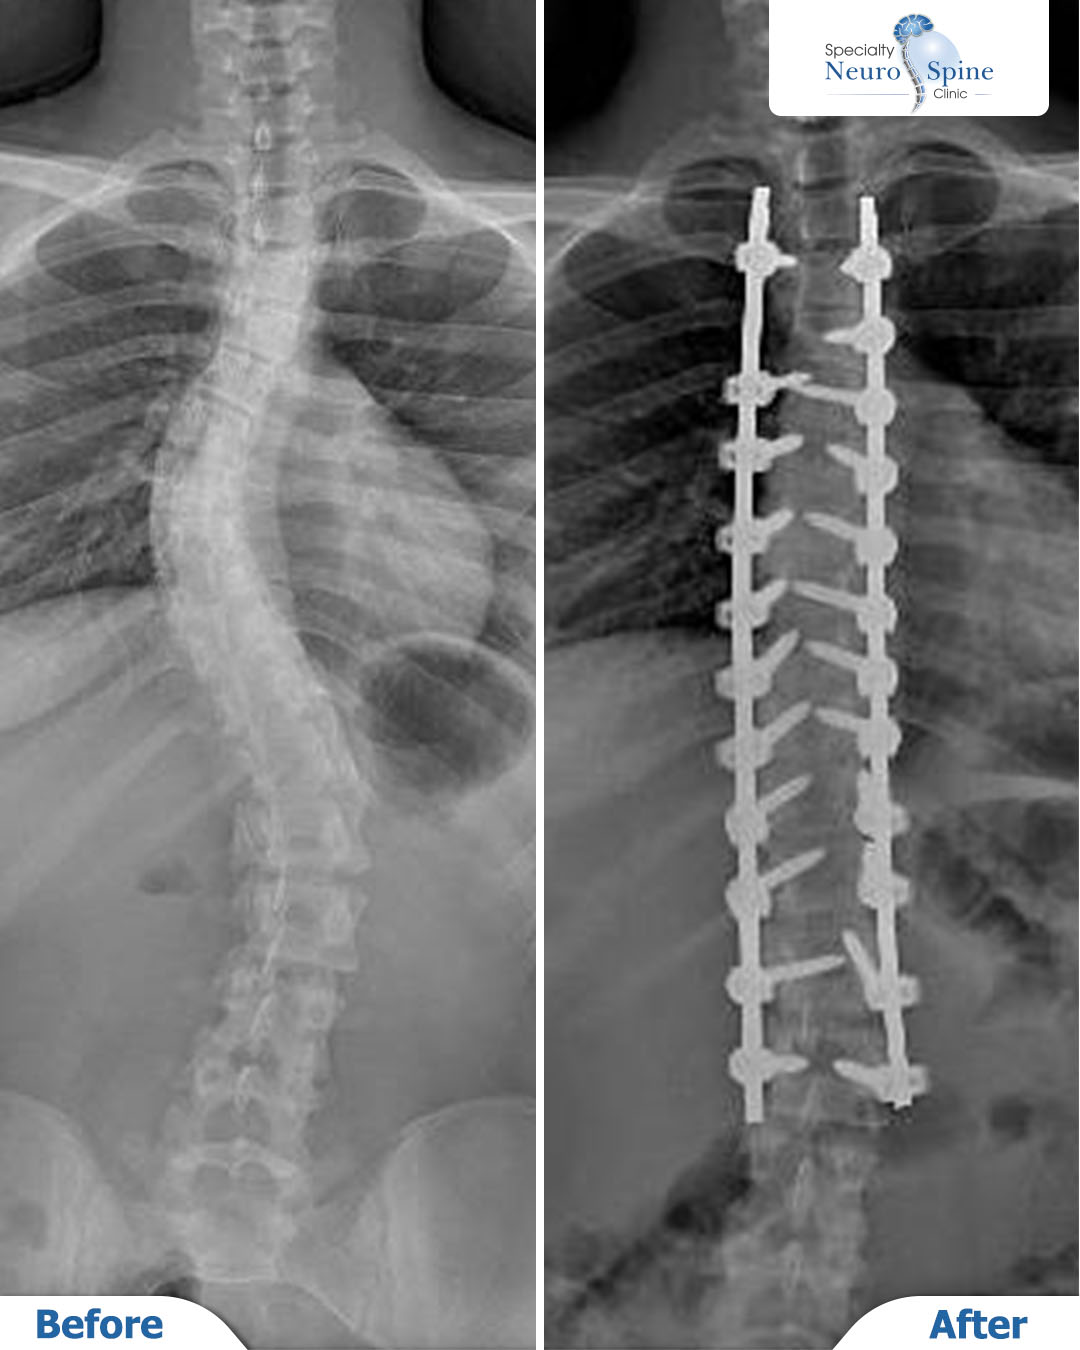

Before and after X-rays of our dear patient Mariam, a 16 years old from Jordan, who underwent spinal fusion surgery from the third thoracic vertebra (T3) to the second lumbar vertebra (L2) using advanced minimally invasive endoscopic techniques.